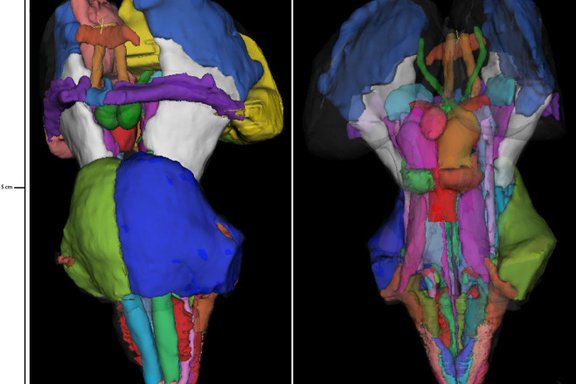

Examples of imaging of the red nucleus and substantia nigra across different field strengths (1.5, 3T, 7T), in vivo or post mortem and with different imaging sequences. Only the two images on the left are acquired in the same person, numbers and outlines indicate labelled structures.